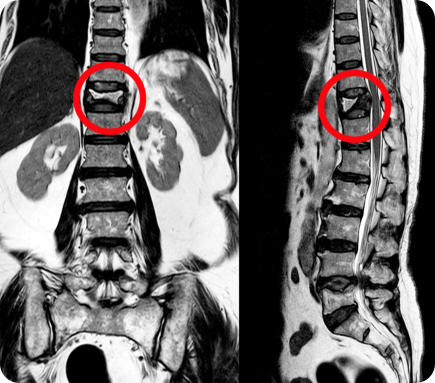

A senior man stands straight holding a box of plants wearing gardening boots and a straw hat X-ray of a spine with a fracture. The fracture is circled in red.

X-ray of a spine with a fracture. The fracture is circled in red.